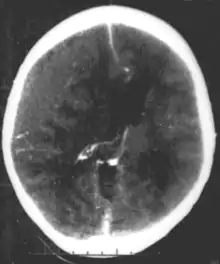

| Epidural hematoma, an example of a focal injury |

- Epidural hemorrhage is bleeding between the dura mater and the skull.[4] It is commonly associated with damage to the middle meningeal artery, often resulting from a skull fracture.